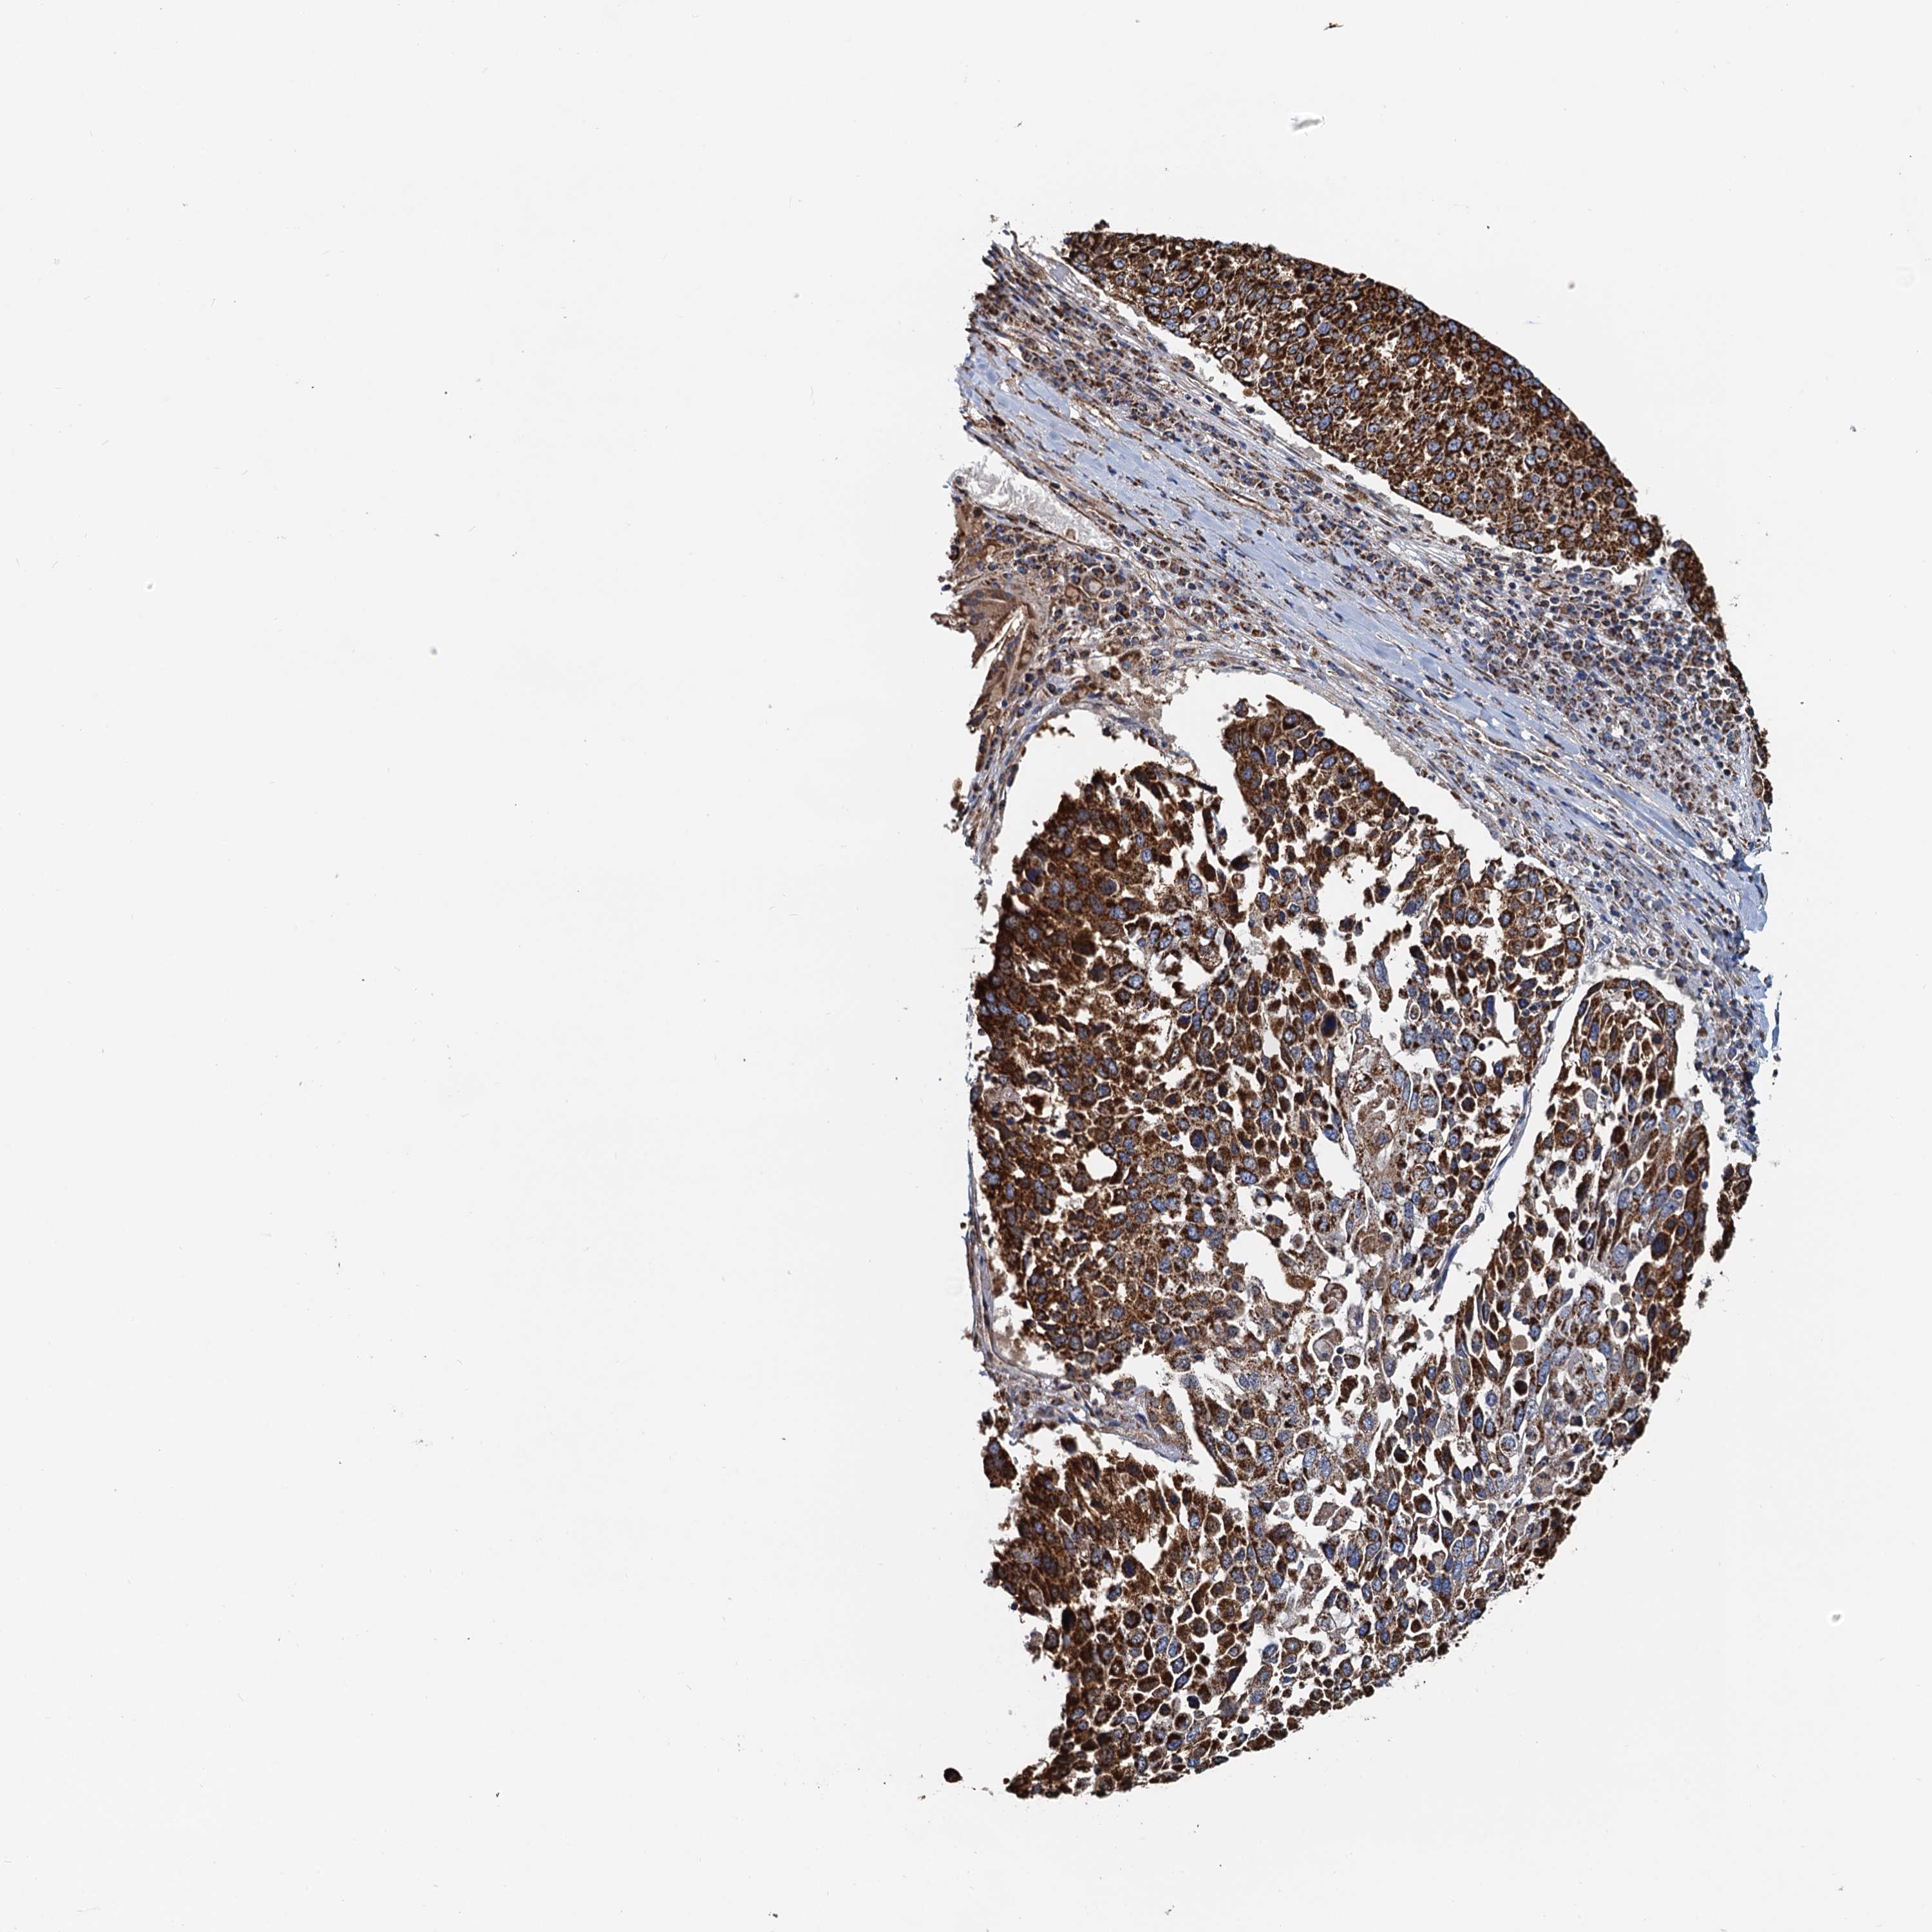

LUNG ADENOCARCINOMA (VALIDATION) - Interactive survival scatter ploti

The Survival Scatter plot shows the clinical status (i.e. dead or alive) for all individuals in the patient cohort, based on the same data that underlies the corresponding Kaplan-Meier plots. Patients that are alive at last time for follow-up are shown in blue and patients who have died during the study are shown in red.

The x-axis shows the expression levels (FPKM) of the investigated gene in the tumor tissue at the time of diagnosis. The y-axis shows the follow-up time after diagnosis (years). Both axes are complimented with kernel density curves demonstrating the data density over the axes. The top density plot shows the expression levels (FPKM) distribution among dead (red) and alive patients (blue). The right density plot shows the data density of the survived years of dead patients with high and low expression levels respectively, stratified using the cutoff indicated by the vertical dashed line through the Survival Scatter plot. This cutoff is automatically defined based on the FPKM cutoff that minimizes the p-score. The cutoff can be changed by dragging the vertical line or by entering a cutoff value in the square labeled "Current cut-off".

Under the Survival Scatter plot the p-score landscape (black curve; left axis) is shown together with dead median separation (red curve; right axis). Dead median separation is the difference in median mRNA expression between patients who have died with high and low expression, respectively. It is calculated as follows: median FPKM expression of dead patients with high expression - median FPKM expression of dead patients with low expression. This is intended to aid the user in visually exploring custom cutoffs and the associated p-scores and dead median separation.

Individual patient data is displayed and can be filtered by clicking on one or more of the category buttons on the top of the page. Categories describing expression level and patient information include: high, low, alive, dead, female, male and tumor stages. The scale of the x-axis can be toggled between linear and log-scale by clicking on the "x log" button. Mouse-over function shows TCGA ID, patient information and mRNA expression (FPKM) for each patient.

& Survival analysisi

Kaplan-Meier plots summarize results from analysis of correlation between mRNA expression level and patient survival. Patients were divided based on level of expression into one of the two groups "low" (under cut off) or "high" (over cut off). X-axis shows time for survival (years) and y-axis shows the probability of survival, where 1.0 corresponds to 100 percent.

AAGAB is not prognostic in Lung Adenocarcinoma (validation)

: 37.03

P scorei

N/A

Average pTPM 41.9

Number of samples 105